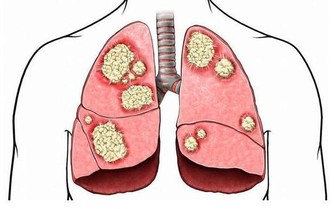

而地球上的一些細菌、病毒等都一直在盯著我們,如腫瘤細胞、乙肝病毒等。

只要我們的抵抗力正常,那麼腫瘤細胞就無法擴散或惡化成癌症,乙肝病毒也會得到很好的抑制。

但當我們的身體免疫力下降時,一直徘徊在我們的身體內外的細菌病毒或者癌細胞,

就會趁著這個「大好機會」在我們的身體搞破壞!

③抵抗力越好的人,得癌症的概率越低。

因為這類人的免疫細胞能夠抑制腫瘤細胞的擴散和惡化,將癌症扼殺在搖籃里。